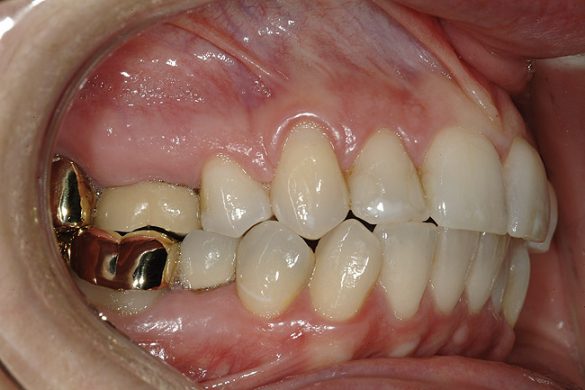

O pacientă în vârstă de 44 de ani s-a prezentat pentru evaluarea şi îmbunătăţirea zâmbetului ei. Acuza principală era reprezentată de afişarea neatractivă a coroanelor posterioare din aur, asociată cu petele albe inestetice de pe dinţii frontali (fig. 1, 2). Scopul ei convingător pentru solicitarea tratamentului a fost acela de a dobândi un „zâmbet deosebit”.

FUNCŢIONAL: La majoritatea dinţilor posteriori ai pacientei ce erau restauraţi cu coroane (fig. 6, 7) era importantă interpretarea minuţioasă a istoricului pacientei şi a rezultatelor evaluării ocluzale. Coroanele din aur de la nivelul 1.7. şi 1.4. prezentau orificii de uzură pe suprafeţele ocluzale, cu semne de minimă uzură pe celelalte coroane posterioare şi la dentiţia naturală. Era evidentă o uzură moderată pe coroana din aur a molarului 4.7.